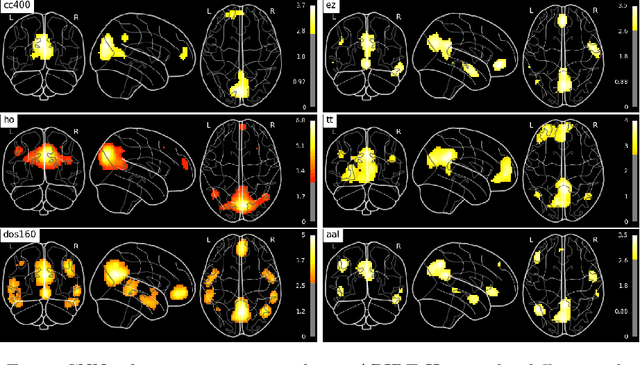

Abstract:Resting-state functional MRI (rs-fMRI) scans hold the potential to serve as a diagnostic or prognostic tool for a wide variety of conditions, such as autism, Alzheimer's disease, and stroke. While a growing number of studies have demonstrated the promise of machine learning algorithms for rs-fMRI based clinical or behavioral prediction, most prior models have been limited in their capacity to exploit the richness of the data. For example, classification techniques applied to rs-fMRI often rely on region-based summary statistics and/or linear models. In this work, we propose a novel volumetric Convolutional Neural Network (CNN) framework that takes advantage of the full-resolution 3D spatial structure of rs-fMRI data and fits non-linear predictive models. We showcase our approach on a challenging large-scale dataset (ABIDE, with N > 2,000) and report state-of-the-art accuracy results on rs-fMRI-based discrimination of autism patients and healthy controls.